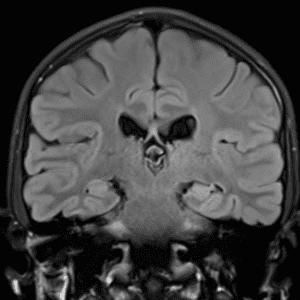

Brain Tumor Practice Cases

Case #3

Ganglioglioma